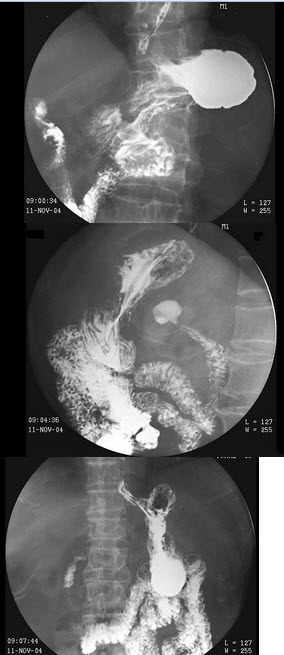

21、单项选择题

女,53岁,常感中上腹不适,结合图像,最可能的诊断为()

A.正常表现

B.慢性胃炎

C.胃溃疡

D.胃憩室

E.胃癌

点击查看答案